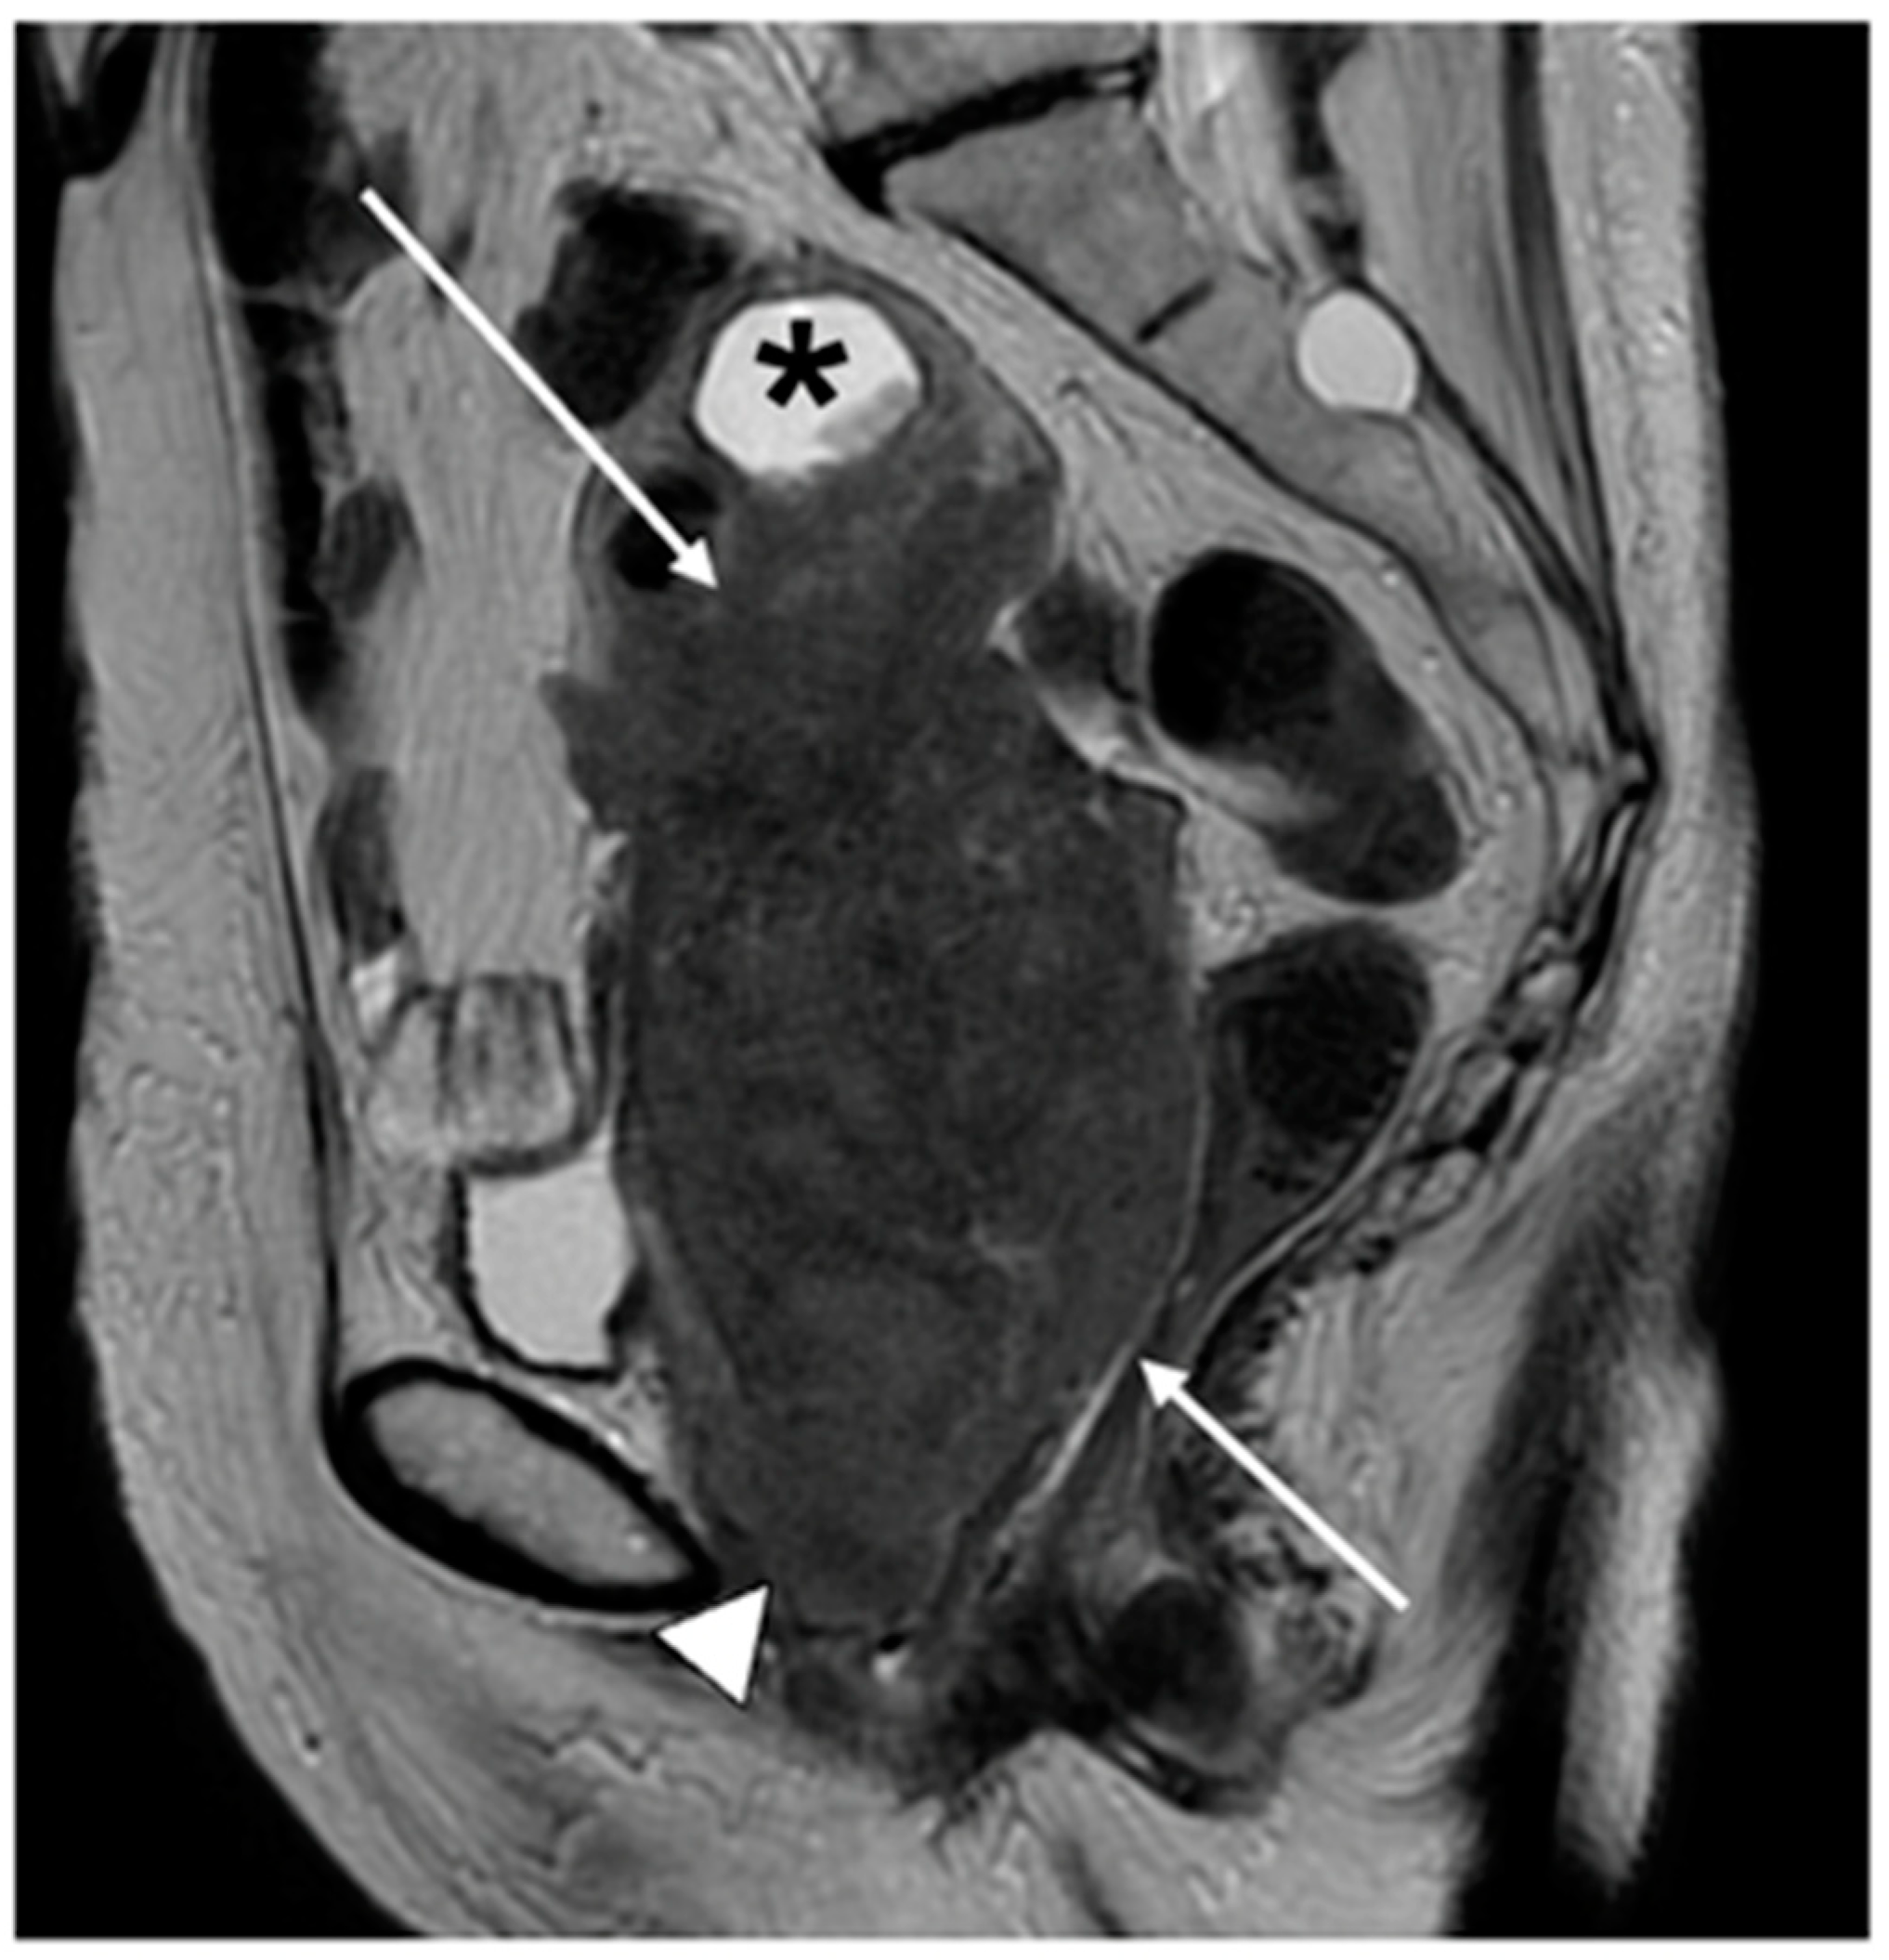

| Stage III | Involves the lower third of the vagina and/or extends to the pelvic wall and/or causes hydronephrosis or non-functioning kidney and/or involves pelvic and/or paraaortic lymph nodes |

| IIIB | Extension to the pelvic wall and/or hydronephrosis or non-functioning kidney (unless known to be due to another cause) |